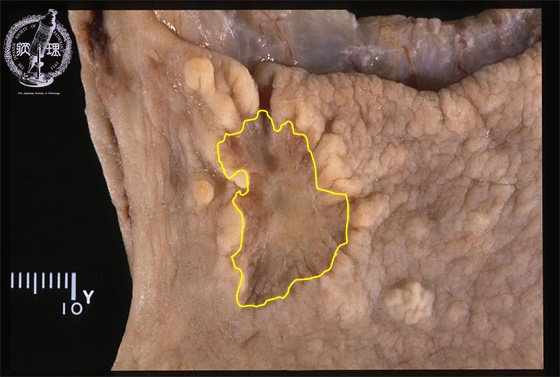

- ★(8)Stomach cancer(early gastric cancer)

Gross appearance: Early (Type 0-IIc) carcinoma measuring 28 x 18 mm and arising in the anterior wall of the gastric antrum. The interface with non-dysplastic mucosa is undulating and the later shows reactive elevation. The lesion has a brownish, depressed and granular surface.